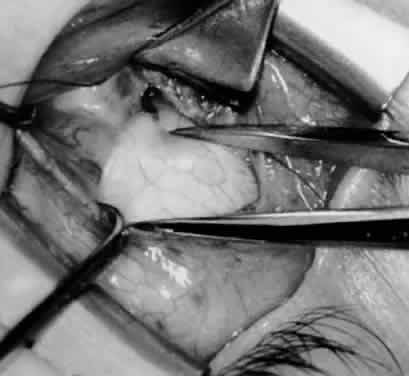

Fig. 13. The inferior oblique muscle is sectioned from the globe. A preplaced 6-0 Vicryl suture is attached to the insertion.

Fig. 14. The inferior temporal vortex vein, 8 mm posterior to the temporal insertion of the inferior rectus muscle, is held on a Green muscle hook.

Fig. 15. The placement of sutures within the sclera for a recession procedure of 10 mm. The anterior suture is placed 3 mm temporal and 2 mm posterior to the lateral insertion of the inferior rectus muscle, and the posterior suture is placed 3 mm further posteriorly.

Fig. 16. Two sutures straddle the inferior temporal vortex vein insertion for a 14-mm recession procedure.

Fig. 17. Knots are tied to show the placement. The inferior oblique muscle is held on a Stevens muscle hook.